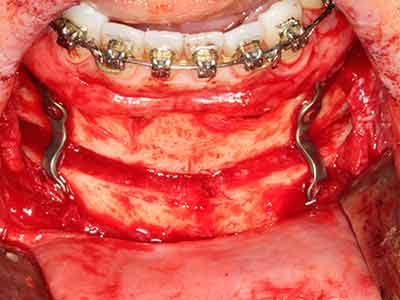

Чисто ортодонтските индикации включват ортогнатна хирургия, генопластика (Фиг. 27-30) и орбитална декомпресия при пациенти с напреднала ендокринна орбитопатия, в резултат от Базедова болест (Ponto, Zwiener et al. 2014). Пиезо апаратите се използват също за лицево-челюстна хирургия и за отстраняване на тумори в основата на черепа в различни болници.